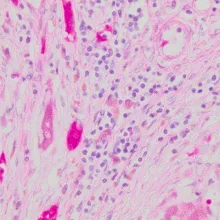

در بافت شناسی، رنگ آمیزی هماتوکسیلین معمولاً به همراه یک رنگ زمینه ای مثل ائوزین انجام می شود؛ از این رو این روش رنگ آمیزی روش H&E نام دارد.

این تکنیک رنگ آمیزی، به طور گسترده ای در مطالعه نمونه های سیتولوژی به ویژه در آزمایش PAP برای تشخیص سرطان دهانه رحم استفاده می شود.

هماتوکسیلین رنگ آبی مایل به بنفش تیره دارد و اسیدهای نوکلئیک را با واکنش پیچیده و ناشناخته رنگ آمیزی می کند و همچنین برای شناخت انواع بافتها و تغییرات مورفولوژیکی که اساس تشخیص سرطان را تشکیل میدهند، استفاده می شوند.

با انواع فیکساتورها به خوبی کار میکند و طیف وسیعی از ویژگیهای سیتوپلاسمی، هستهای و ماتریکس خارج سلولی را نشان میدهد.